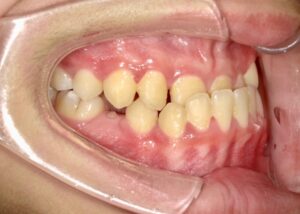

側面

- Before